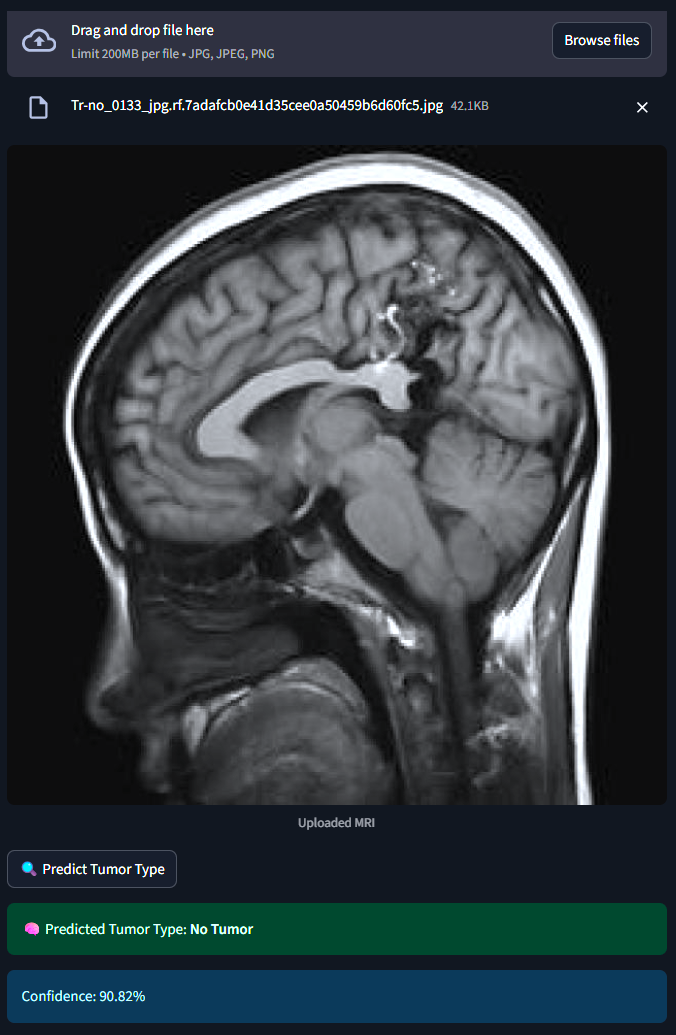

The system classifies MRI brain scans into one of four categories - Glioma, Meningioma, Pituitary Tumor or No Tumor. It uses both a Custom Convolutional Neural Network (CNN) and MobileNetV2 Transfer Learning for classification. An interactive Streamlit web app allows users to upload MRI images and receive real-time tumor predictions with probability scores.

1) Dataset :- 2,443 MRI images labeled and categorized by medical experts. 2) Preprocessing :- Used ImageDataGenerator for rescaling, rotation, zoom and flipping to augment limited data. 3) Model 1 (Custom CNN) :- Built from scratch with 3 convolutional layers, dropout and softmax classification. 4) Model 2 (MobileNetV2) :- Fine-tuned transfer learning model using pretrained ImageNet weights. 5) Training :- Used callbacks like EarlyStopping and ModelCheckpoint to optimize training and avoid overfitting. 6) Evaluation :- Tracked model performance using confusion matrix, accuracy/loss plots, and classification reports. 7) Deployment :- Developed a Streamlit web app for real-time image classification and visualization.